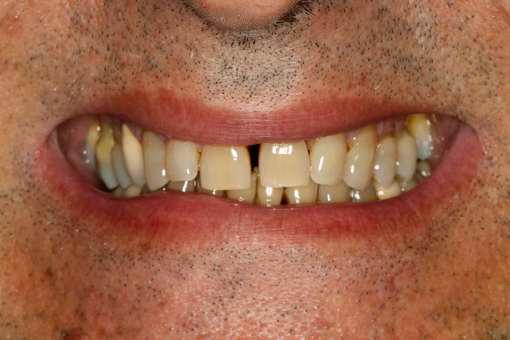

Negli ultimi anni sono presenti in letteratura studi che riportano riabilitazioni implantoprotesiche effettuate in questa tipologia di pazienti , fornendo loro nuove prospettive terapeutiche.

Con una pianificazione attenta, una collaborazione multidisciplinare e l’applicazione di linee guida aggiornate, anche le persone con MEC, possono ricevere le cure odontoiatriche necessarie, mantenendo la salute orale e potendo esibire con serenità un bel sorriso!